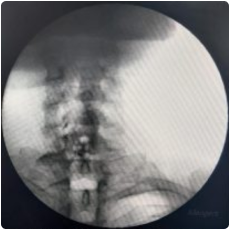

image 911

Intraop fluoroscopy image of needle placement at the cervical facet